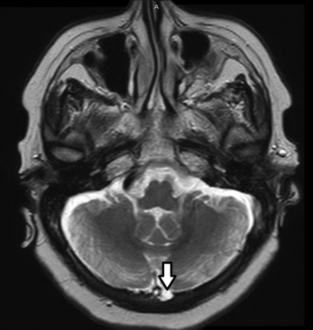

Es la dilatación marcada de la cisterna magna generando ensanchamiento de la fosa posterior, no acompañada de alteraciones cerebelosas (►Fig. 8).11 La megacisterna puede presentar expansión posterior, inferior o lateral y es atravesada por vasos venosos innominados, tributarios del seno longitudinal inferior.11 El diagnóstico diferencial debe realizarse con:11

(A-B) TC, corte axial de cerebro (A). Aumento del diámetro de la cisterna Magna (*). Nótese la presencia de estructuras vasculares venosas en su interior (flecha). RM, cortes sagital axial ponderado en T2 (B) se objetiva aumento de los diámetros de la cisterna Magna (*) atravesada por estructuras vasculares (flecha).